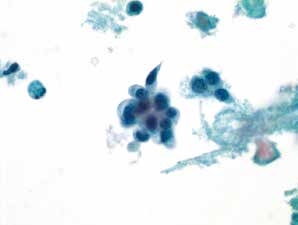

图4-65 非角化型鳞癌(高倍、液基、巴氏染色)

明显的肿瘤素质,癌细胞成团,形态多样,核大,深染,染色质粗颗粒状,胞质蓝染。

图4-66 非角化型鳞癌(高倍、液基、巴氏染色)

与图4-65为同一病例的不同视野,注意背景中的肿瘤素质十分明显。